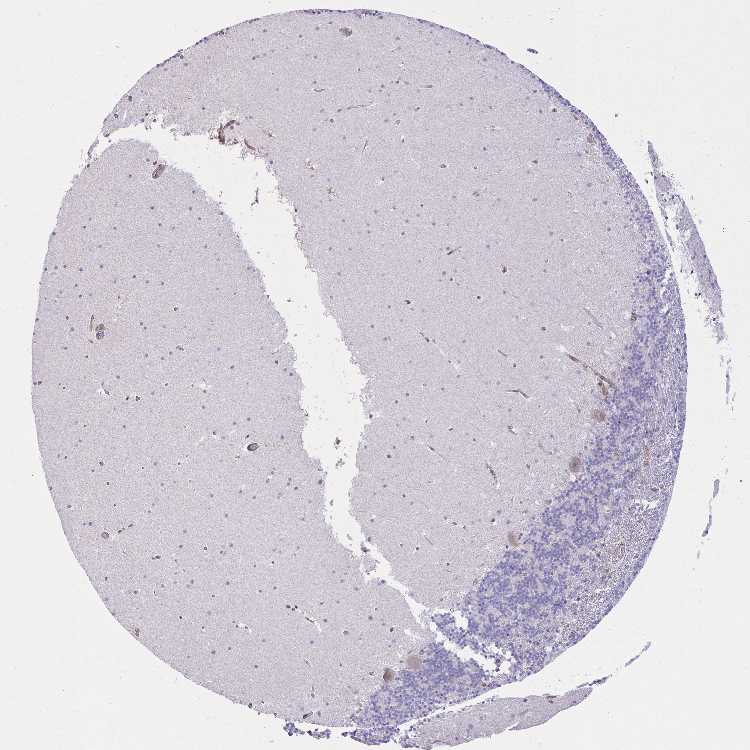

CEREBELLUM - Antibody stainingi

Antibody staining in the annotated cell types in the current human tissue is reported as not detected, low, medium, or high, based on conventional immunohistochemistry profiling in selected tissues. This score is based on the combination of the staining intensity and fraction of stained cells.

Each image is clickable and will lead to virtual microscopy that enables deeper exploration of all samples and also displays staining intensity scores, fraction scores and subcellular localization as well as patient and tissue information for each sample.

Antibody HPA051476Antibody HPA054698Antibody CAB016780

Purkinje cells MediumNot detectedHigh

Cells in granular layer LowNot detectedNot detected

Cells in molecular layer Not detectedNot detectedNot detected